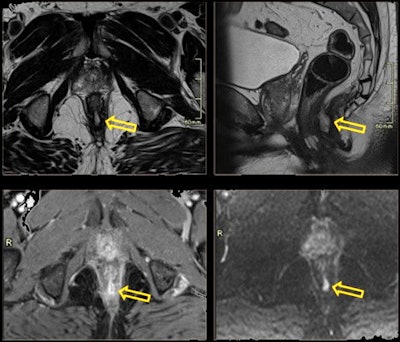

68-year-old man with rectal fistula presented for prostate screening and complained of rectal discomfort. Posterior fistula and abscess were discovered.- Presacral fibrosis: Presacral soft tissue is found in up to half of patients after treatment for rectal cancer.